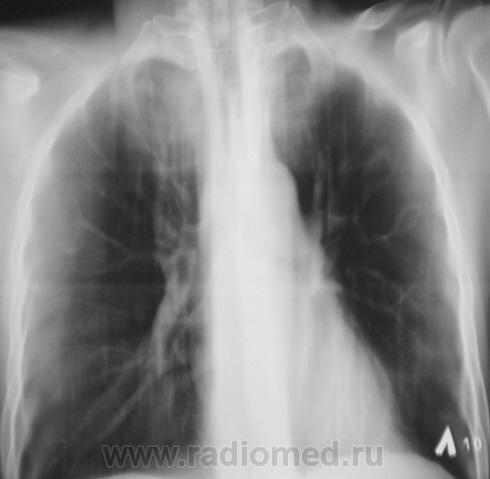

Следущий контроль (сегодня).

Мы трактовали это как крупноочаговые тени.

Осенне-весеннее обострение...

подождите, а курса лечения то чем?антибиотиками или специфического у фтизиатров?

У фтизиатров лечение, у них, родимых.